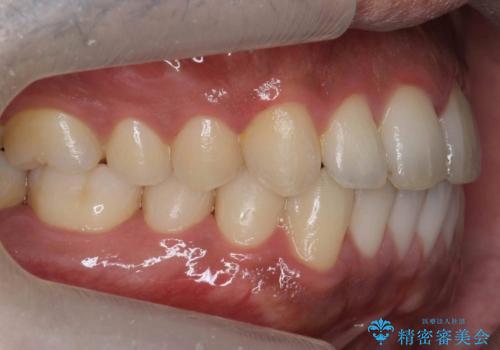

前歯が反対にかんでいる 部分ワイヤーとインビザラインの併用で短期治療

- 前歯の並びを気にして来院。

前歯が一本奥に入っているのを乗り越えるにはワイヤー矯正が治療期間も短く、歯に負担が少なく有利と説明しました。

上はワイヤー部分矯正、下はインビザラインの部分矯正コースを行いました。